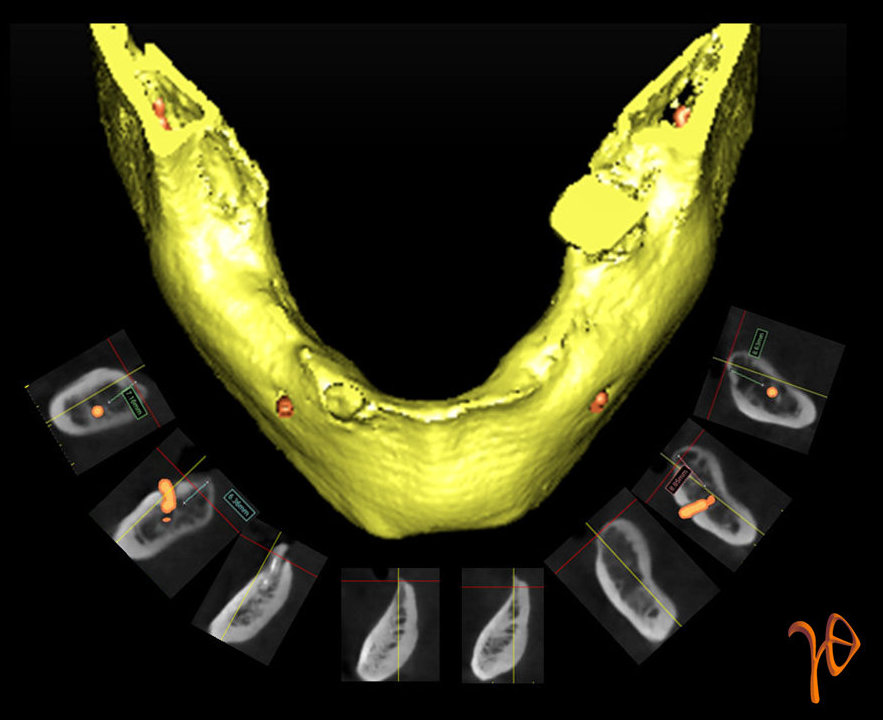

Από την ανάλογη μελέτη της κάτω γνάθου (Εικόνα 4), προέκυψε σχέδιο για τοποθέτηση τεσσάρων εμφυτευμάτων, εκ των οποίων τα δύο με τέτοια κλίση ώστε να αποφευχθεί ο τραυματισμός των γενειακών νεύρων(θέσεις #35 και #45)(Εικόνα 5).

Εικόνα 4. Μελέτη όλων των cross-sections για το ύψος, το εύρος, την κλίση του οστού και την σχέση με το κάτω φατνιακό και το γενειακό νεύρο.

Εικόνα 5. Τρισδιάστατη ανασύνθεση(Simplant) των θέσεων επιλογής για την τοποθέτηση των εμφυτευμάτων. Σημειώστε την σχεδίαση των #35 και #45 σε σχέση με το γενειακό νεύρο, αλλά και των δύο προσθίων σε σχέση με την οξύαιχμη γναθική ακρολοφία.